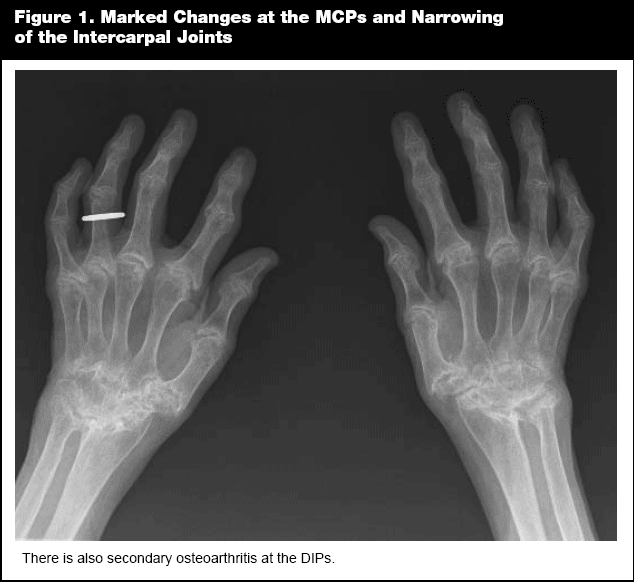

Chronic synovial inflammation at the C1-C2 junction can lead to atlanto-axial instability with potentially severe consequences that are described later in this article. Of particular interest to the primary care practitioner making a decision about a patient's suitability for surgery requiring anesthesia, is the fact that cervical spine instability in patients with RA may make intubation a very complicated and dangerous procedure.

Advanced synovial inflammation of the atlanto-axial joint mandates an examination of the x-rays of the cervical spine in flexion and extension by an experienced radiologist. Instability of the upper cervical joints may pose a potentially lethal complication for an RA patient if he/she suffers even minor whiplash or other neck trauma since the spinal cord is not protected as in someone with a normal C-spine. There are pre- and peri-operative complications possible in these patients if advanced changes of cervical spine subluxation or cranial settling are present. (See Figure 2.) This is especially true during intubation or while moving the patient around during anesthesia.

Orthopedic surgery plays an essential role in the treatment of patients with RA. One of the most important advances in treatment of RA in the last half century is the development and perfection of joint replacement. Replacement of hips and knees are especially gratifying since many thousands of arthritis patients who would otherwise have to use canes, crutches, or walkers, or stay in bed or require wheel chairs can walk normally with little or no disability or pain. Replacement of other joints including elbows, shoulders, ankles, and finger joints are improving at a rapid rate and have an important place in treatment of RA. Orthopedic surgeons' contributions are very important in other conditions brought on by RA including repair of ruptured tendons, arthroscopic joint repairs, and procedures that improve function and cosmetic appearance of hands and feet. It is occasionally necessary to stabilize the neck at C1-C2 location because of the erosion and laxity of ligaments normally holding the spine in alignment caused by RA. Either a neurosurgeon or an orthopedist specializing in the spine may have to fuse these joints and the skull to protect the patient from life-threatening spinal injury.